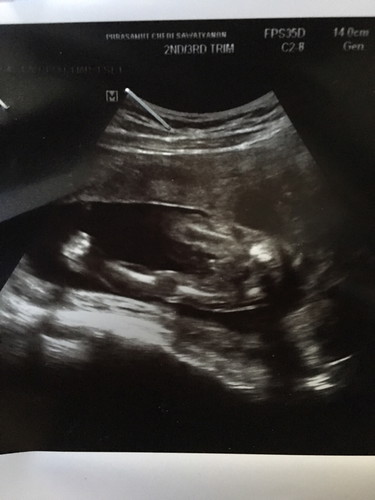

ใครมองออกมั่งคะว่าเพศอะไร แล้วส่วนไหนคือส่วนไหนพอดีดูไม่เป็น

ดูผ่านๆคิดว่าชาย ดูไปดูมาเราคิดว่าปลายเท้าน้องอ่ะค่ะ🤔เพราะน้องงอขาข้างนึง

ชายค่ะ.. จู๋อยู่ตรงกลาง ให้คิดภาพน้องนอนอ้าขาอยู่ค่ะ

ชายค่าา เห็นขาสองข้าง แล้วก็อะไรเเว็บๆ 555

น่าจะชายนะค่ะ เห็นจู๋โผล่ออกมาเลย😁

น่าจะเป็นผู้ชายนะคะ เห็นเป็นแหลมๆ

น่าจะผู้ชายนะแม่ เห็นจู๋น้อยๆ😆

คิดว่าชายนะคะ ค่อยข้างชัดเลย